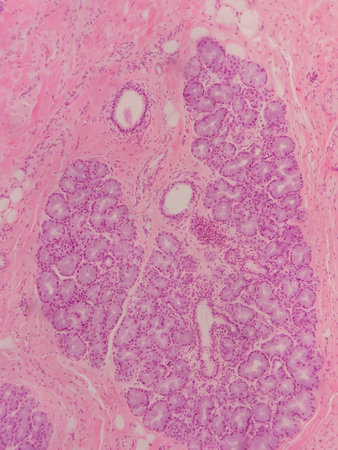

Photomicrograph showing histological features of benign prostatic hyperplasia. Enlarged prostate gland with nodular proliferation of glandular and stromal components.

Photomicrograph showing histological features of benign prostatic hyperplasia. Enlarged prostate gland with nodular proliferation of glandular and stromal components.